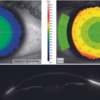

Además de la información sobre la curvatura corneal, la elevación y la potencia refractiva, el software de cribado del queratocono proporciona información importante sobre las superficies corneales anterior y posterior. Este análisis preoperatorio es esencial en cirugía refractiva para evitar complicaciones postoperatorias relacionadas con la ectasia corneal.

Basándose en la información paquimétrica y de elevación, el VX210 permite a los profesionales visualizar y analizar la posición de los anillos intraestromales, que son útiles para corregir ciertas formas de queratocono y errores refractivos.